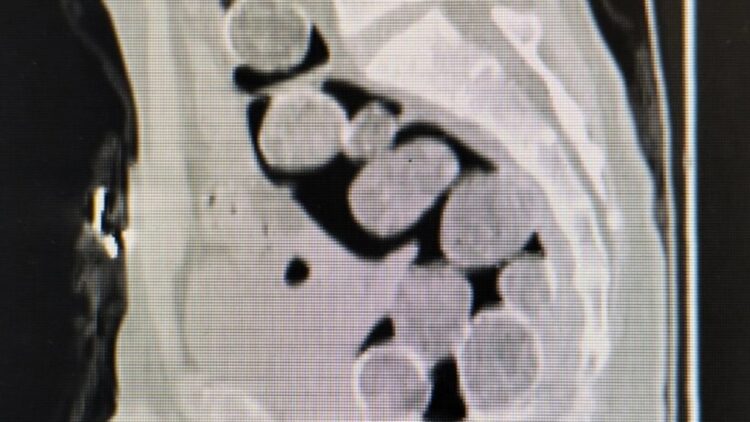

Samsun Eğitim ve Araştırma Hastanesi’ne götürülen şüphelilerin çekilen röntgen filminde, mide ve bağırsaklarında yabancı madde olduğu tespit edildi.

A.A. ve H.T’ye yapılan tıbbi müdahale sonucunda 18 paket halinde 500 gram sentetik uyuşturucu ele geçirildi. Gözaltına alınan şüphelilerin ikametlerinde yapılan aramada ise ruhsatsız tabanca ve 99 fişek bulundu.